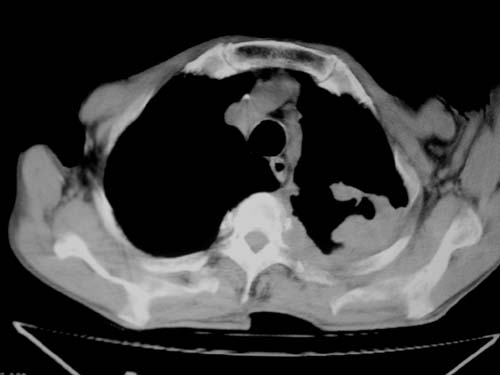

标题: CT19736:男,76岁,咳嗽,胸痛 [打印本页]

标题: CT19736:男,76岁,咳嗽,胸痛

支持左上肺周围型肺癌并空洞形成伴胸椎转移。z左下肺炎

左上肺癌性空洞伴胸椎转移。